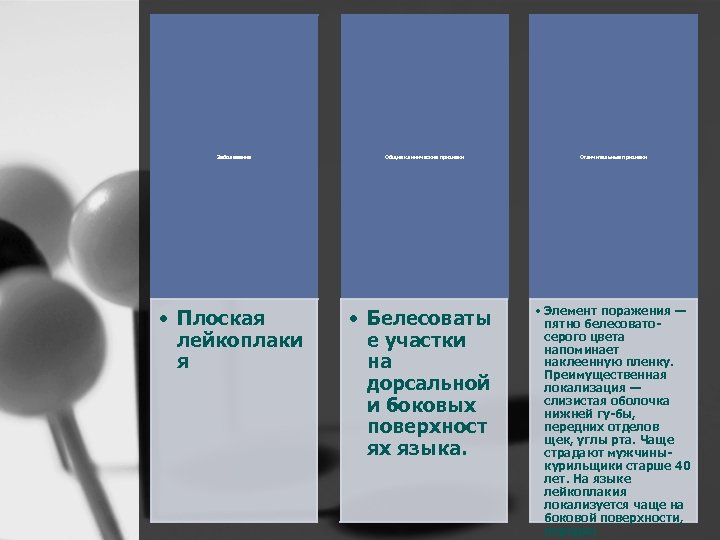

Заболевание • Плоская лейкоплаки я Общие клинические признаки • Белесоваты е участки на дорсальной и боковых поверхност ях языка. Отличительные признаки • Элемент поражения — пятно белесовато серого цвета напоминает наклеенную пленку. Преимущественная локализация — слизистая оболочка нижней гу бы, передних отделов щек, углы рта. Чаще страдают мужчины курильщики старше 40 лет. На языке лейкоплакия локализуется чаще на боковой поверхности, нередко